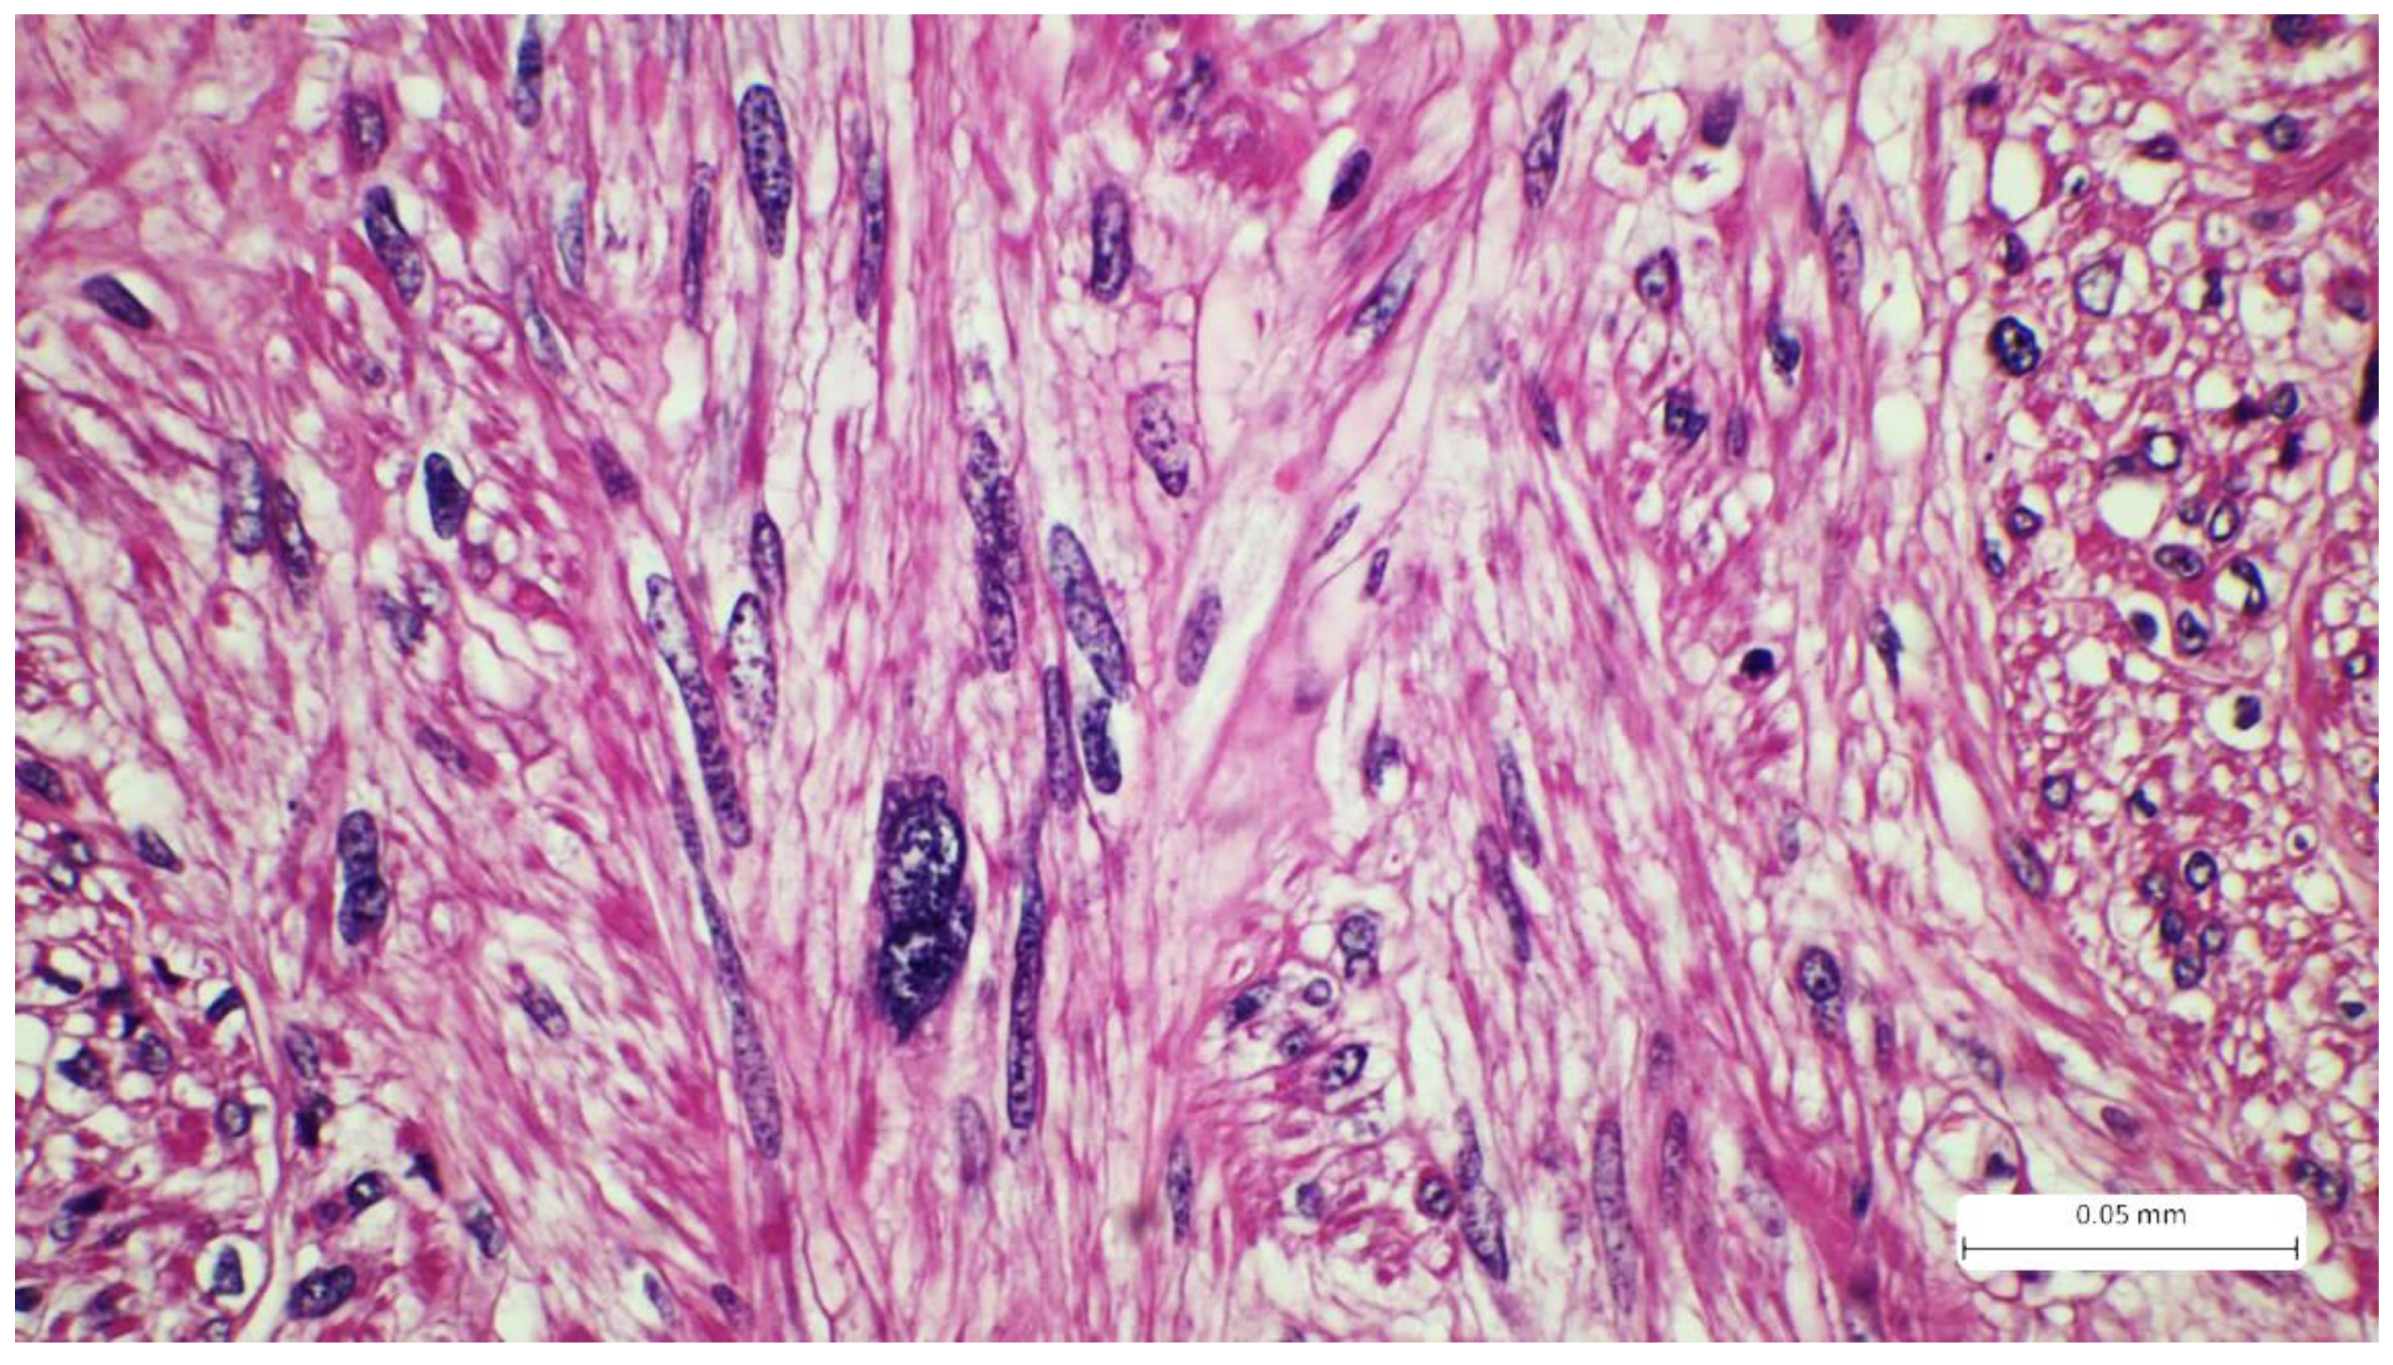

2. Case Report